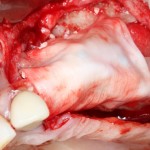

Графт адаптируется (с помощью скальпеля), устанавливается в нужное положение. Для этого, опять же, очень удобно использовать аналоги имплантов из имплантологического набора (в крайнем случае, остеотомы или пины параллельности):

Напомню, нет необходимости заполнять графтом всю лунку. Тем более — полость удаленной кисты или гранулемы. Поэтому 100 мг вполне хватает, чтобы аугментировать лунку любого объема.

Благодаря своим свойствам. Bio-Oss Collagen не забивается в подготовленную лунку импланта, не съезжает и не сползает при его установке: